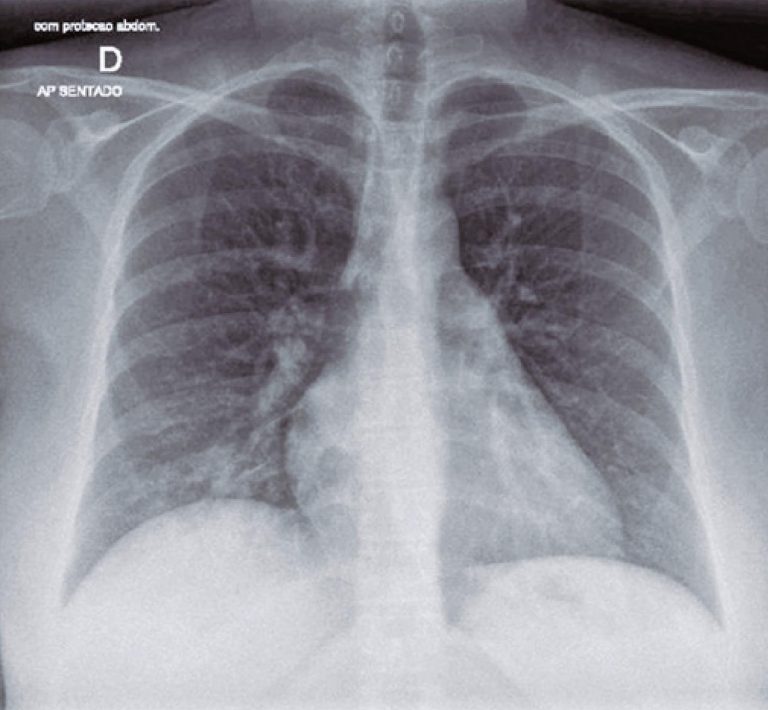

ABSTRACT The coronavirus disease 19 (COVID-19) is responsible for the current worldwide pandemic. Treatment and prophylaxis are still under investigation. Convalescent plasma therapy could be an alternative. We report a case of a 41-year-old patient, at 28 weeks of gestation, was hospitalized with COVID-19. On the 10th day after onset of symptoms, the clinical picture worsened, and she required high-flow oxygen therapy (30L/minute), with 92% oxygen saturation, and chest X-ray showing mild bilateral opacities at lung bases. Blood tests showed […]